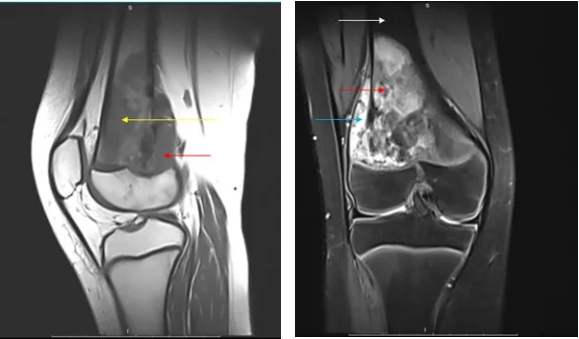

2024 年,17 岁的少年陈捷(化名)因右腿持续疼痛就医,MRI 检查显示股骨下端巨大占位,活检确诊为高度恶性骨肉瘤。更令人揪心的是,肺部 CT 发现双肺散在分布 12 枚转移灶,最大直径达 2.5 厘米 —— 这意味着肿瘤已进入晚期,传统治疗手段预后极差。

治疗第 2 个月复查显示,肺部转移灶开始出现中央空洞化;第 4 个月,CT 扫描证实所有肺结节完全消失,原发肿瘤体积缩小 83%。这一结果远超预期,为保肢手术创造了条件。术中冰冻病理显示,肿瘤组织 95% 以上呈坏死改变,切缘阴性。术后继续巩固治疗 3 个月,患者目前已恢复正常生活,复查肿瘤标志物持续阴性。